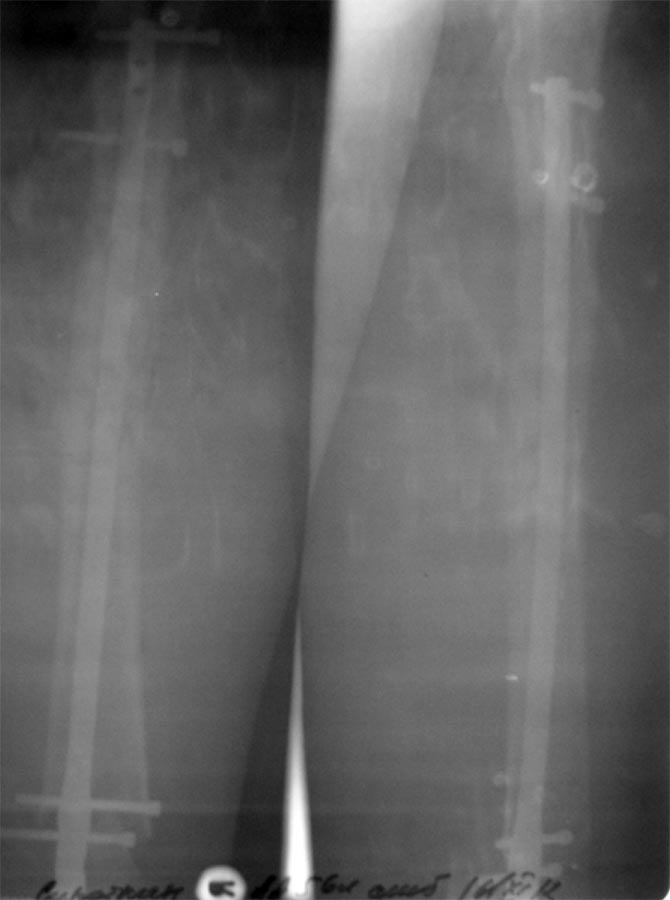

Разрешите представить Вам следующий случай.Пациент С., 55 л, получил открытый сегментарный перелом бедренной кости 24.07.12 в результате столкновения скутера с автомобилем (упал со скутера). Доставлен в наше отделение. В экстренном порядке- наложение стержневого АВФ, ПХО раны. После ее заживления,17.08.12- ретроградный БИОС универсальным бедренным штифтом ChM. Блокирующие винты перепроведены 05.09.12 (у оператора не хватило опыта-не попал в отверстия). Выписан 28.09.12. В настоящий момент беспокоят боли в коленном суставе, отек всей конечности, отсутствие полного объема движений в суставе, субфебрилитет. Ходит на костылях с нагрузкой примерно 15 % массы тела, увеличить нагрузку мешает боль. Местная температура не повышена, в полости сустава жидкости нет.Результаты анализов-СОЭ, СРБ пока неизвестны. Что делать?

На мой взгляд, боли в суставе возможны по двум причинам: ось бедра не востановлена, имеется вальгусная отклонение голени, из-за чего неравномерное распределение нагрузки на уже артрозный сустав! Или же изначальное повреждение внутренних структур сустава. Но складывается еше ощущение, что гвоздь не добит сантиметров на 1,5. На мой взгляд, целесообразно произвести диагностическую артроскопию. Исправлять ось, реостеосинтез!

Насчет оси - гвоздь в дистальном отломке идет несоосно ему, на уровне перелома гвоздь ближе к латеральной стенке, то есть эпиметафиз смещен медиально. По профилю - и кзади. Похоже, и укорочение есть.